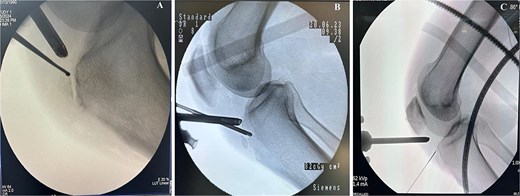

Preoperative MRI was used to determine the mediolateral position of the ossicles, using the femoral condyles as landmark relative to the tibial ossicles. Fluoroscopic guidance was also used intraoperatively to identify the level of the tibial ossicle in a lateral X-ray (Fig. 3) with the help of an 18 gauge spinal needle (Fig. 4).

Intraoperative fluoroscopy views show ossicle before excision and complete removal. (A) Case 1. (B) Case 2. (C) Case 3, marking the position of the ossicle using arthroscopic spinal needle.